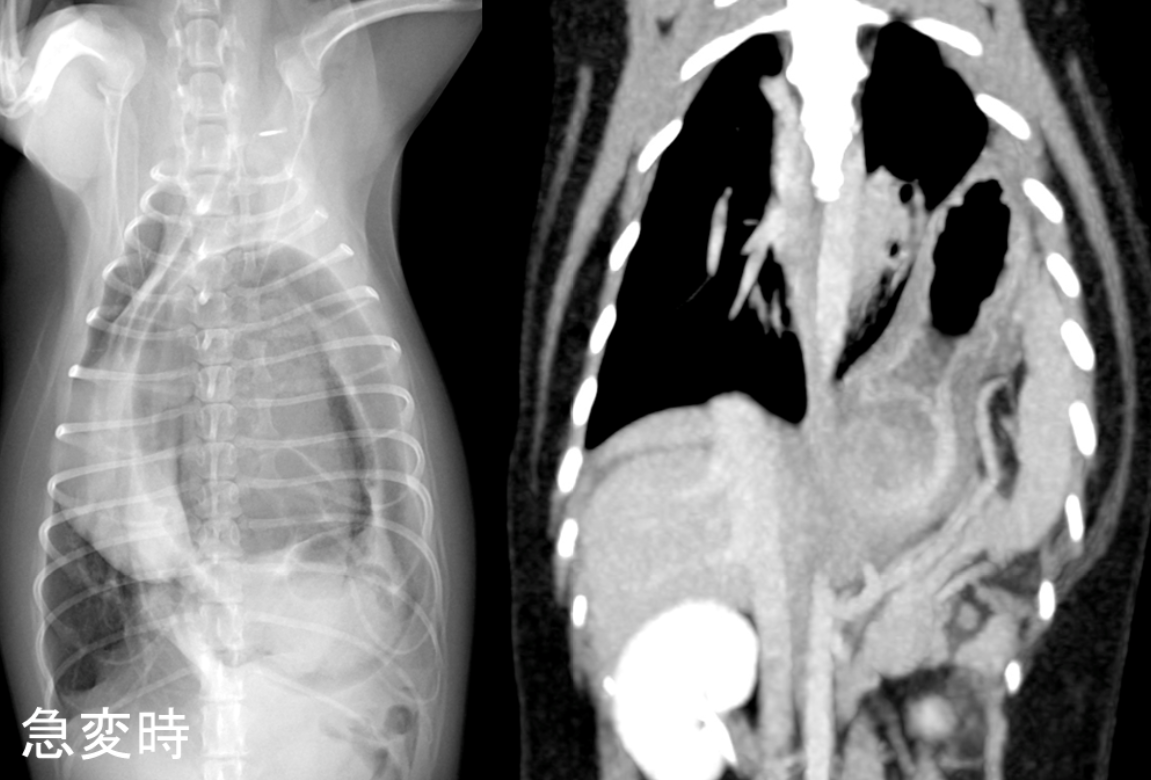

しかし、新たに胃が胸腔内へ脱出し、胃の中に異常に空気がたまってしまったことから、心臓が押され肺がうまく広がらなくなり、突然ショック状態を引き起こしてしまいました。

急変時のレントゲン画像(右)、CT画像(左)